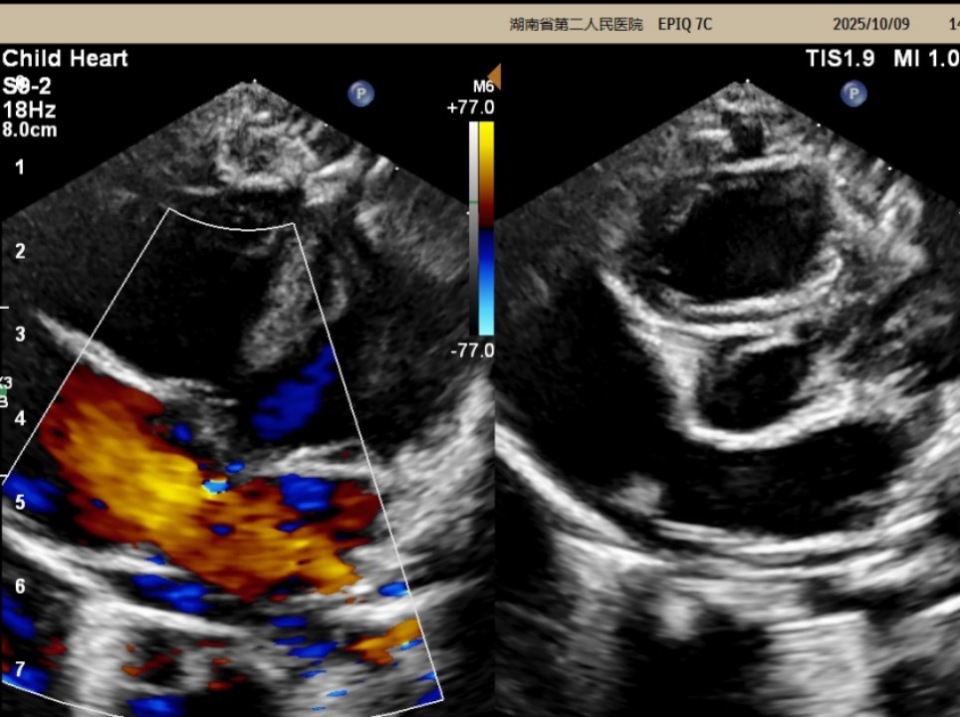

在赵源主任医师的耐心解释下,欣欣妈妈最终还是带宝宝来到超声医学科进行了心脏彩超检查,检查发现:先天性心脏病——房间隔缺损(继发孔型)。

图片

△心脏彩超检查结果